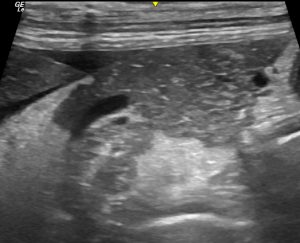

To continue the problematic subject of ‘can an ultrasonographic diagnosis of pancreatitis can be made with any confidence?’, I thought I might post some images of specific cases without history and invite comments.

Maybe you’d like to score this on a scale 1 to 5 where 1 = no evidence pancreatitis and 5 = definite pancreatitis. And ideally give reasons.

I don’t think you can form an optinion from this image. Initial inspection with local fat reaction draws the eye but looking to the left of the image the fat shows achostic enhancement and to the top right the the fat appears normal. The pancreas itself shows changes at the mid- bottom section of the image but otherwise is fairly homogenous.

I think when scanning this patient I would be looking for another cause for the fat reaction before concluding pancreatitis.

I would probably give it a 4. Although we don’t have a scale in the image, I would subjectively think the pancreas is enlarged (compared to the abdominal wall) and overall hypoechoic. The bottom margins are not regular. i agree with Ben as it looks mostly affected on the middle/bottom areas. Peripancreatic reactive fat and some free fluid around the liver border. So definitely focal peritonitis and changes in pancreas enough to be highly suspicious of pancreatitis. Of course, other causes should be ruled out before drawing conclusions.

I would be thinking that post-hepatic portal hypertension with oedema of the pancreas and abdominal fat is a plausible explanation for pancreatic hypoechogenicity and contrasting hyperechoic fat.

The ascites will also cause hyperechoic change in abdominal fat. Since that tends to be a fairly, evenly-distributed diffuse effect I suspect that it’s due to some change in the tissues. Although a purely physical effect on sound transmission also seems a possible factor to me,

The wider picture is that this kind of thing tends to make me feel that the hypoechoic pancreas/hyperechoic fat pattern isn’t specific for any one pathology.